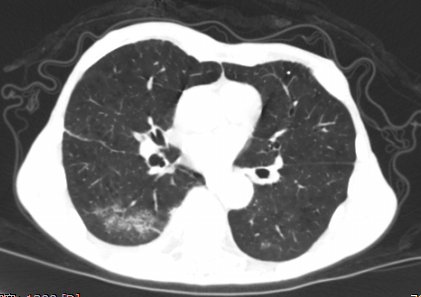

首次检查

第 4 天复查,两肺内病灶较前密度减低、消散;